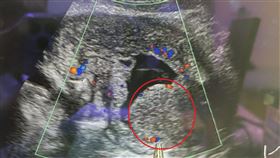

7旬嬤反覆血尿疼痛治不好 竟罹罕癌第3期

台中一名70多歲的李姓婦人,因長期反覆小便疼痛、血尿...

8旬翁尿不出來 X光驚見400克巨大結石

高雄市一名81歲的老翁長期有排尿困難的問題,到醫院泌...